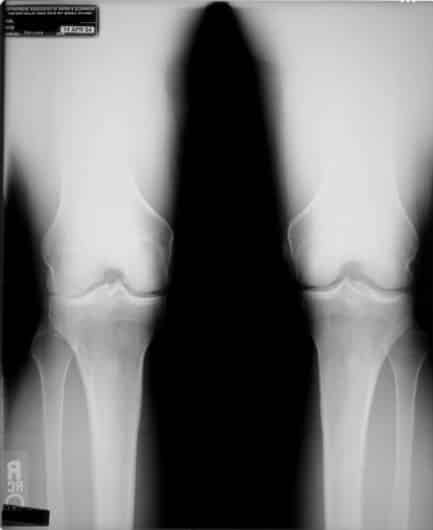

Zie hieronder een röntgenfoto voor een voorbeeld. Zoals u kunt zien is een deel van het kraakbeen van de rechterknie weggesleten (links op de foto). Hierdoor staat de knie naar binnen. Maar wat was er eerst, de slijtage van het bot of de stand van de knie?

Deze röntgenfoto is van een cliënt van een Egoscue-kliniek (de methode waarop houdingstherapie is gebaseerd) in Austin, Texas. Deze is aan de slag gegaan met uitsluitend houdingstherapie-oefeningen. Iets meer dan een jaar later heeft hij weer röntgenfoto’s laten maken. Zie de foto hieronder.